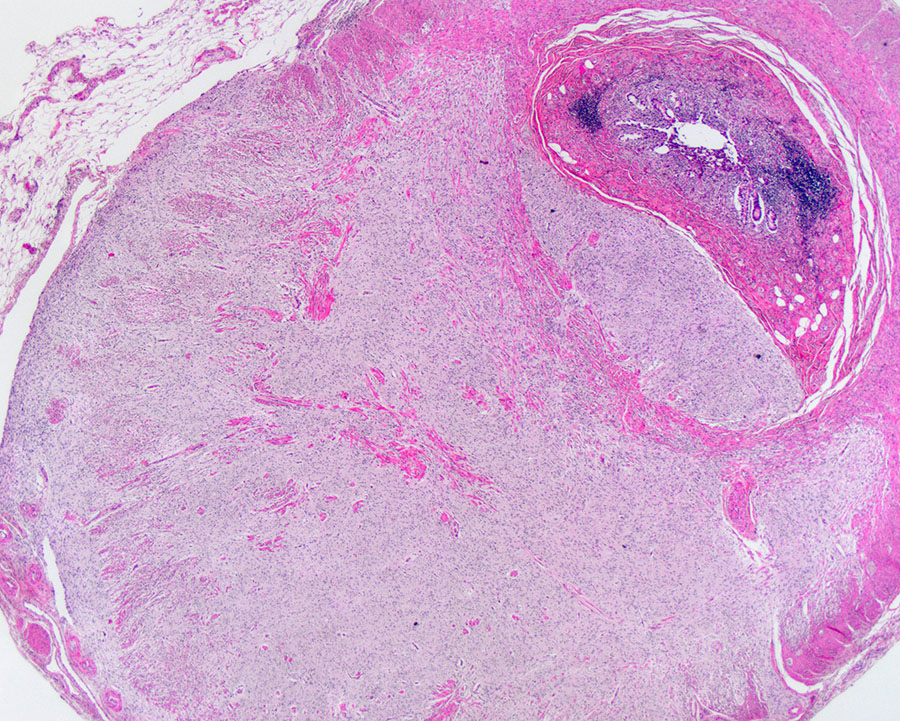

Microscopic examination of the appendix demonstrated a well-circumscribed lesion within the appendiceal wall (Figure 1A). The lesion was predominantly composed of a proliferation of cells with amphophilic to clear cytoplasm and bland spindled to wavy nuclei (Figure 1B). There were also scattered larger cells with abundant eosinophilic cytoplasm, some with granular cytoplasmic pigment, and eccentrically placed round nuclei with vesicular chromatin and prominent nucleoli (Figure 1C). No mitotic figures or cytologic atypia were identified. Immunohistochemical analysis showed the spindled cells and larger cells were highlighted by S-100 protein (Figure 1D), while only the larger cells were positive for synaptophysin (Figure 1E).